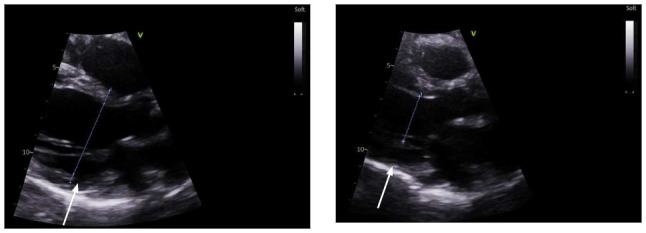

左心室游离壁破裂是心肌梗死的致命并发症。尽管紧急手术修复是首选治疗方法,但修复方法仍高度个性化。本报告介绍了一例特纳综合征患者自发性冠状动脉夹层导致左心室游离壁破裂的病例,该患者在心肺旁路手术中使用 EVARREST 纤维蛋白密封补片无缝合技术成功修复了左心室游离壁。

Left ventricular free wall rupture is a lethal complication of myocardial infarction. Although emergent surgical repair is the treatment of choice, the method of repair remains highly individualized. This report presents a case of spontaneous coronary artery dissection in a patient with Turner syndrome that led to left ventricular free wall rupture and was successfully repaired on cardiopulmonary bypass using a suture-free technique with the EVARREST Fibrin Sealant Patch.